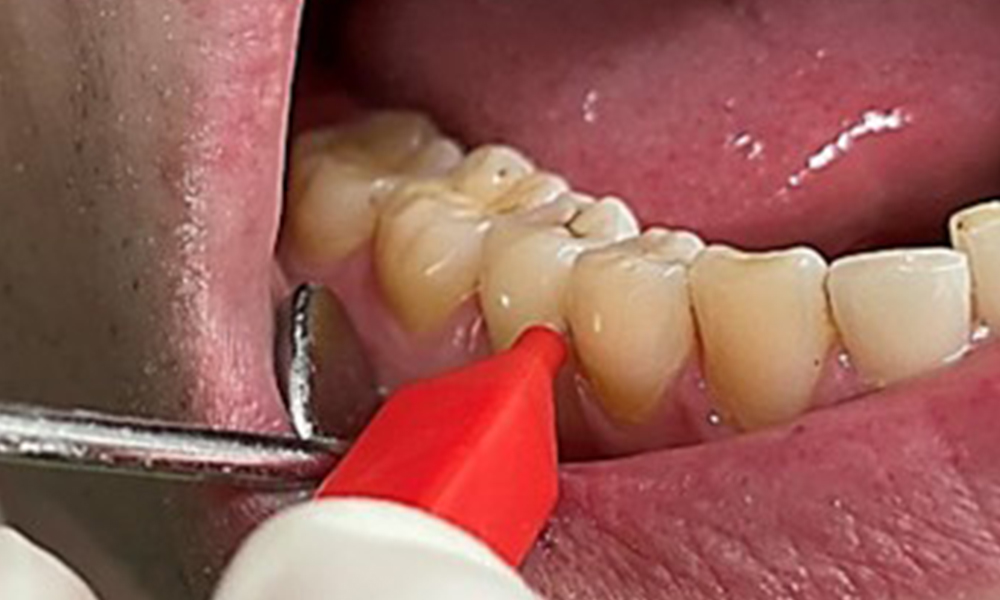

Anwendung der Interdentalbürstchen in Rg 44/45

Abb. 9: Anwendung der Interdentalbürstchen in Rg 44/45, © Dr. R. Krapf

Zugleich ist es notwendig die Interdentalraumbürstchen, welche der

Patient täglich verwendet nach der richtigen Größe zu überprüfen und den Patienten zu bestärken diese konsequent zu benutzen (Abb. 9). Eine

gute Mundhygiene ist unabdingbar, um das Parodontitisrisiko durch das Rauchen zu minimieren.